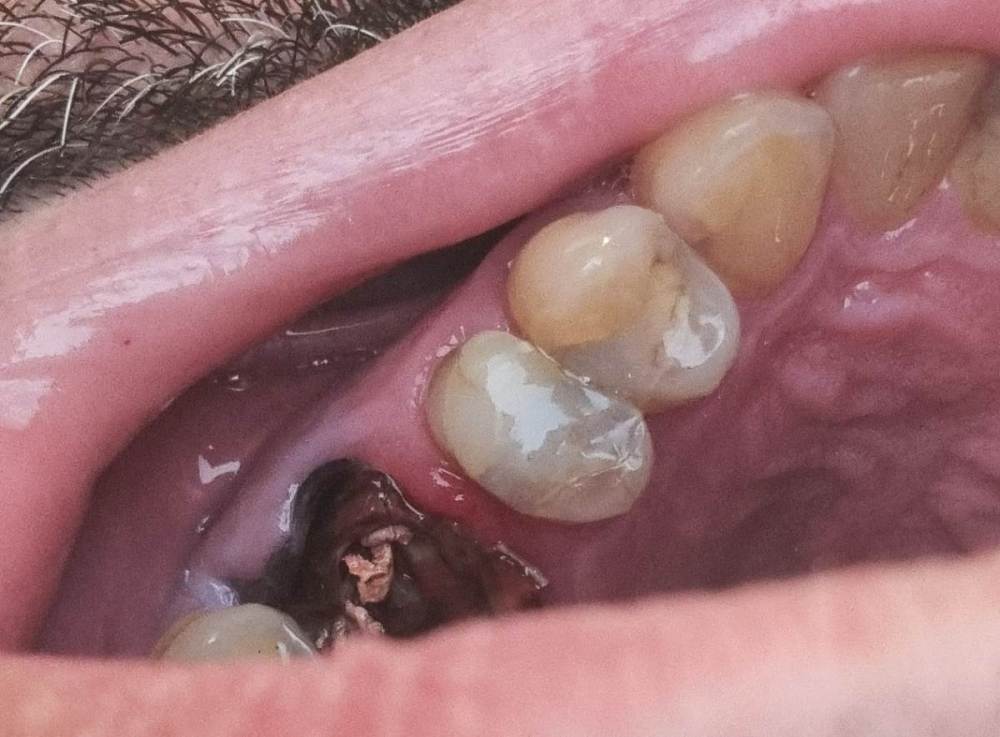

Окончательно упала коронка  металлопласт с 26го зуб, которая простояла 28 лет. 10 лет  назад она уже падала и ее восстановили на штифте. Хочу поставить новую коронку, либо на штифте, а лучше на культевой вкладке. Наверное, надо перецементировать каналы. Что стоит делать с зубом по фото и во сколько можно уложиться?